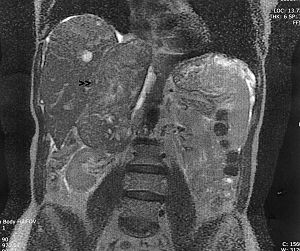

Liver cancer, also known as hepatic cancer, is a cancer which starts in the liver, rather than migrating to the liver from another organ or section of the body. In other words, it is a primary liver cancer.

Cancers that originate elsewhere and eventually reach the liver are known as liver metastasis or secondary liver cancers, and are most commonly from cancer of the gastrointestinal (GI) tract (colon cancer), lung cancer, renal cancer (cancer of the kidney), ovarian cancer and prostate cancer.